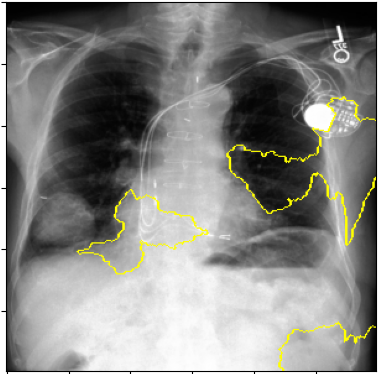

3.3 Interpretability

Post-Hoc Comparisons. We compare our concept-based explanations to post-hoc XAI techniques LIME and SHAP, applied to the baseline InceptionV3 model. The image explanations generated by these techniques disagree with each other and the medical ground truth. We show an example of this observation in Figure 7, where both techniques fail to capture the large mass in the X-ray, and highlight irrelevant regions such as areas outside of the lung as incorrectly important to the classification decision. In contrast, our approach correctly identifies the presence of a mass. More examples are shown in Figure 10.

Refer to caption

(a) Ground Truth

(b) LIME

(c) SHAP

(d) CXR-LLaVA Generated Report

(e) Our Approach

Figure 7: Example of our explanation approach outperforming LIME, SHAP and CXR-LLaVA. Ground truth (a) is a “Large right upper zone mass". LIME (b) and SHAP (c) fail to capture the mass in the X-ray. Most important image regions are bounded by yellow for LIME, and shown in more vibrant green for SHAP. CXR-LLaVA (d) generates a report which wrongly describes the image as non-cancerous. Our approach (e) correctly identifies the presence of a mass.